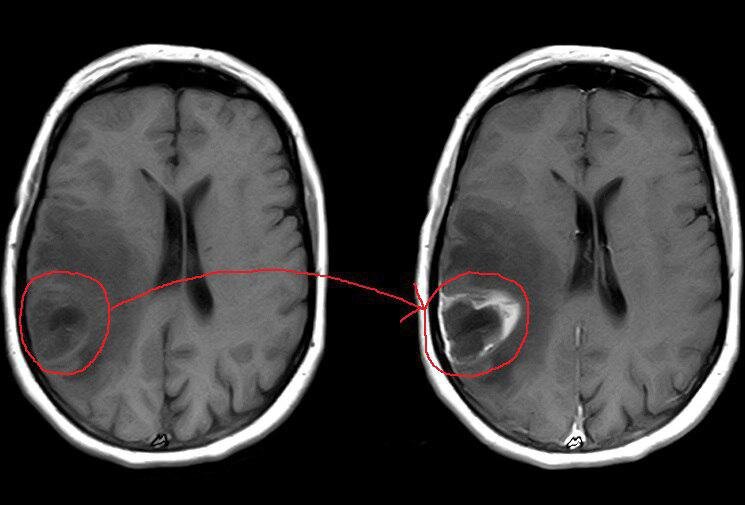

Немного наглядного материала: опухоль после введения контраста видна гораздо лучше. Теперь можно оценить её истинные размеры на фоне зоны отека